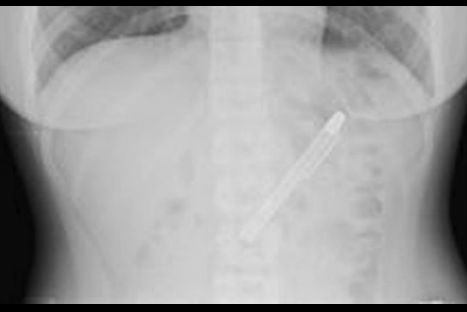

Shing Fang, una joven sufrió alrededor de seis meses un profundo dolor en el estómago que no la dejaba comer por lo que decidió ir al hospital, sin embargo el diagnostico que le dieron en distintos centros de salud era de depresión.

Sin embargo, en el hospital de Taipei, en Taiwán, luego de sacarle una radiografía le dijeron que tenía un lapicero, según comentó la joven no recordaba como es que habría llegado el objeto hasta allí.